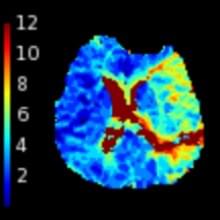

Perfusion imaging-based tissue-level collaterals predict ischemic lesion net water uptake in patients with acute ischemic stroke and large vessel occlusion

Faizy T, et al. (2021) JCBFM Feb 8;271678X21992200. doi: 10.1177/0271678X21992200.

CT perfusion core and ASPECT score prediction of outcomes in DEFUSE 3

Kim-Tenser M, et al. (2020) Int J Stroke Mar 31;1747493020915141. doi: 10.1177/1747493020915141.